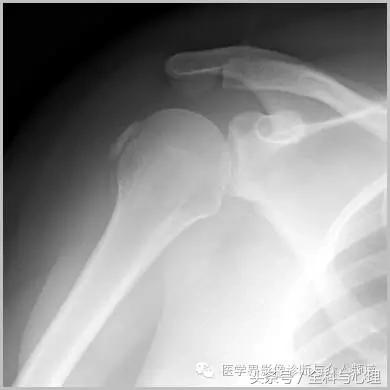

六、肌腱钙化/滑囊炎并钙化

肩关节最常见:肱二头肌长头、肩峰下滑囊钙化,可伴有急性疼痛、肿胀,局部压痛。

肱二头肌肌腱钙化(肩周炎)

肩周炎